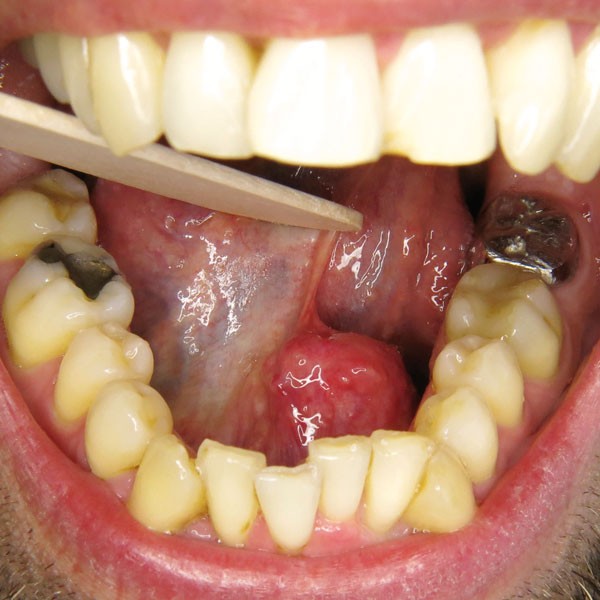

La lithiase est libérée du canal aux ciseaux de Metzenbaum, ce qui permet son énucléation en un seul fragment de plus de 2 cm de grand axe (fig. 6).